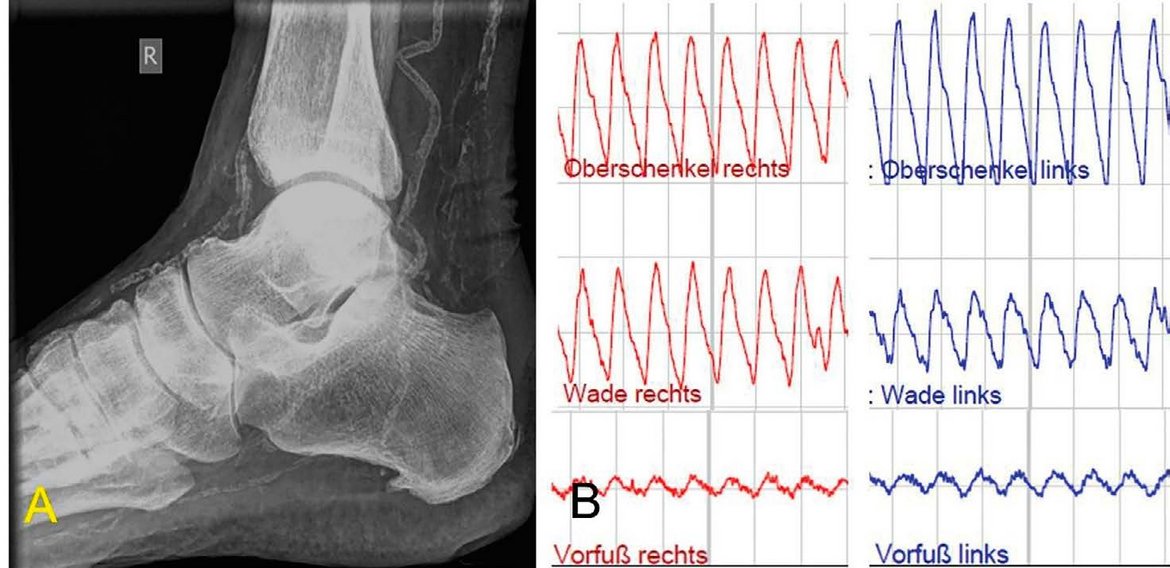

Die Oszillographie der unteren Extremitäten ist ein etabliertes, nicht-invasives Funktionsverfahren zur objektiven Beurteilung der arteriellen Strombahn. Im klinischen Kontext dient sie primär der Detektion und Verlaufsbeobachtung der peripheren arteriellen Verschlusskrankheit (pAVK). Das Prinzip basiert auf der volumetrischen Erfassung pulsabhängiger Druckschwankungen: Über segmentale Manschetten an Knöcheln, Unterschenkeln oder Oberschenkeln werden die Volumenänderungen der Arterien bei jedem Herzschlag registriert. Ein hochempfindlicher Drucksensor wandelt diese mechanischen Impulse in grafische Oszillogramme um. Die diagnostische Auswertung stützt sich auf die Analyse der Amplitudenhöhe sowie der Kurvenmorphologie. Während steile Anstiege auf eine intakte Gefäßelastizität hinweisen, deuten abgeflachte oder deformierte Kurvenverläufe auf hämodynamisch relevante Stenosen oder Verschlüsse hin. Gegenüber der palpatorischen Pulsprüfung bietet die Oszillographie den entscheidenden Vorteil der untersucherunabhängigen Dokumentation und hohen Reproduzierbarkeit. Da das Verfahren ohne ionisierende Strahlung oder invasive Eingriffe auskommt, eignet es sich hervorragend als Screening-Instrument. Es liefert präzise Daten über die funktionelle Kapazität des arteriellen Systems und ergänzt die bildgebenden Verfahren um wertvolle hämodynamische Informationen.

Seit März 2026 steht in der Klinik für Fuß- und Sprunggelenkchirurgie ein modernes Oszillographiesystem zur Verfügung